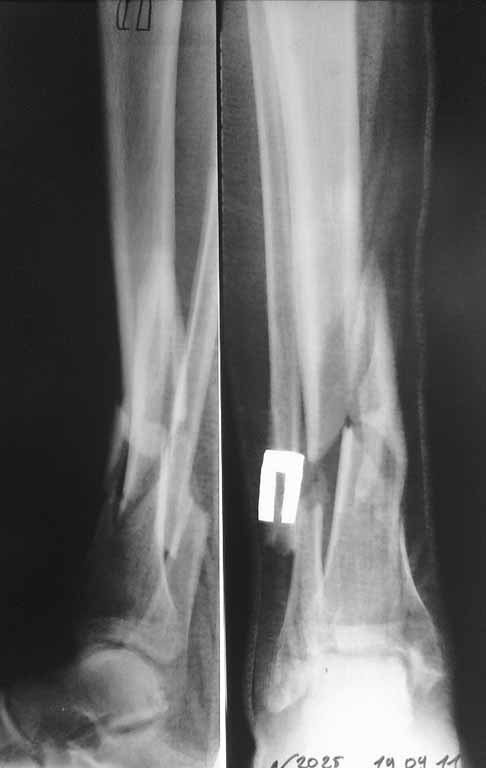

Re: Перелом бедра и голени

спасибо за участие. Перелом голени выложил сегодня из-за проблем с интернетом. На этой неделе запланирована попытка синтеза бедра, длинный PFN ChM, на ортопедическом столе, все-таки планирую открывать зону перелома сразу. Голень на следующей неделе.